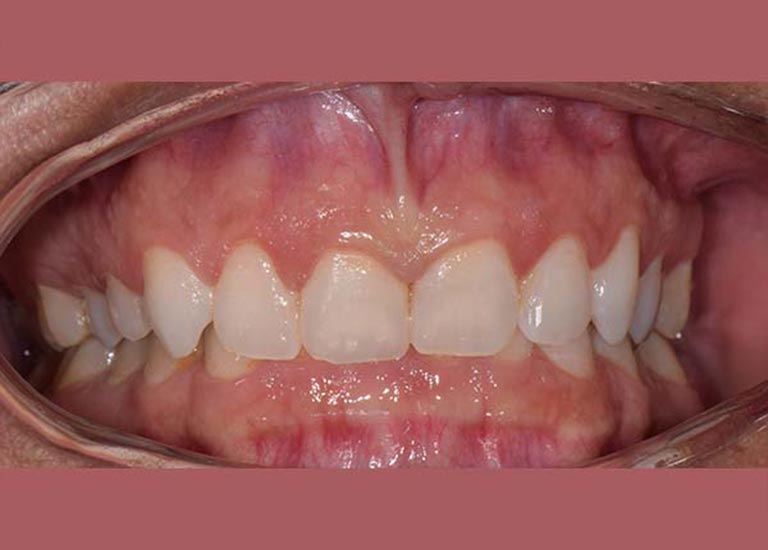

AFTER

Examination revealed a severe deep bite, covering almost all parts of the lower teeth, in addition to a severe backward tilt in her upper front teeth, which affected the beauty of her smile.

Our lady was treated using fixed braces, the tilt in her upper front teeth was adjusted, and the space of their coverage was reduced.

At the end of the treatment, she was able to smile with comfort and confidence again